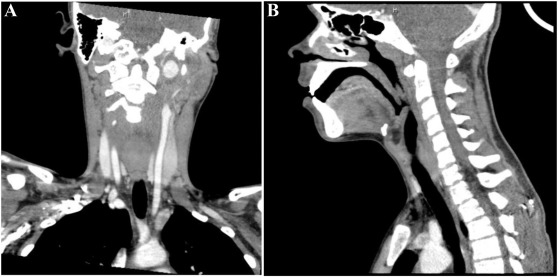

Happy Sunday! Check out this fascinating case about an internal carotid artery pseudoaneurysm presenting as a peritonsillar abscess in a 14-year old with persistent sore throat and emesis after dental work. sciencedirect.com/science/articl…

"The patient's original pharyngitis was thought to have developed into a cellulitis, creating a phlegmon that rapidly compromised and eroded into the carotid sheath, leading to separation of the internal carotid artery walls and the development of the pseudoaneurysm."

"Cases like this illustrate the need to keep internal carotid artery pseudoaneurysms in the differential, especially given children's susceptibility to infectious arteritis "